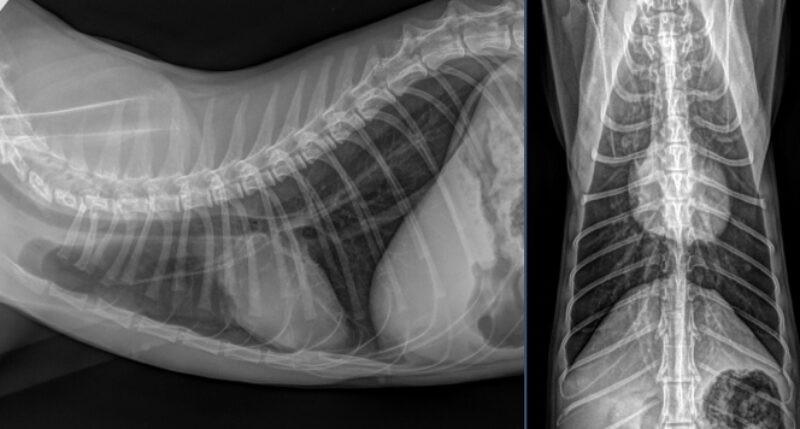

Besten Dank für die Übermittlung dieses spannenden Falles! Es liegen Röntgenbilder des Thorax und des Abdomens in 2 Ebenen vor (sinistro-dextraler Strahlengang, sowie ventro-dorsaler Strahlengang). Wesentliche Hauptbefunde sind im Bereich des muskuloskelettalen Systems, als auch im Abdomen zu vermerken.

Trachea/Ösophagus, Mediastinum, Pulmonalgefäße, Aorta/V.cava, Pleuralraum, sowie alle abgebildeten ossären Strukturen stellen sich unauffällig dar. Die Herzsilhouhette misst im VHS 7,5 Wirbelkörper. Das Thoraxröntgen stellt sich somit unauffällig dar, ohne Hinweis auf Rippenfrakturen, Pneumothorax oder Lungenkontusionen.